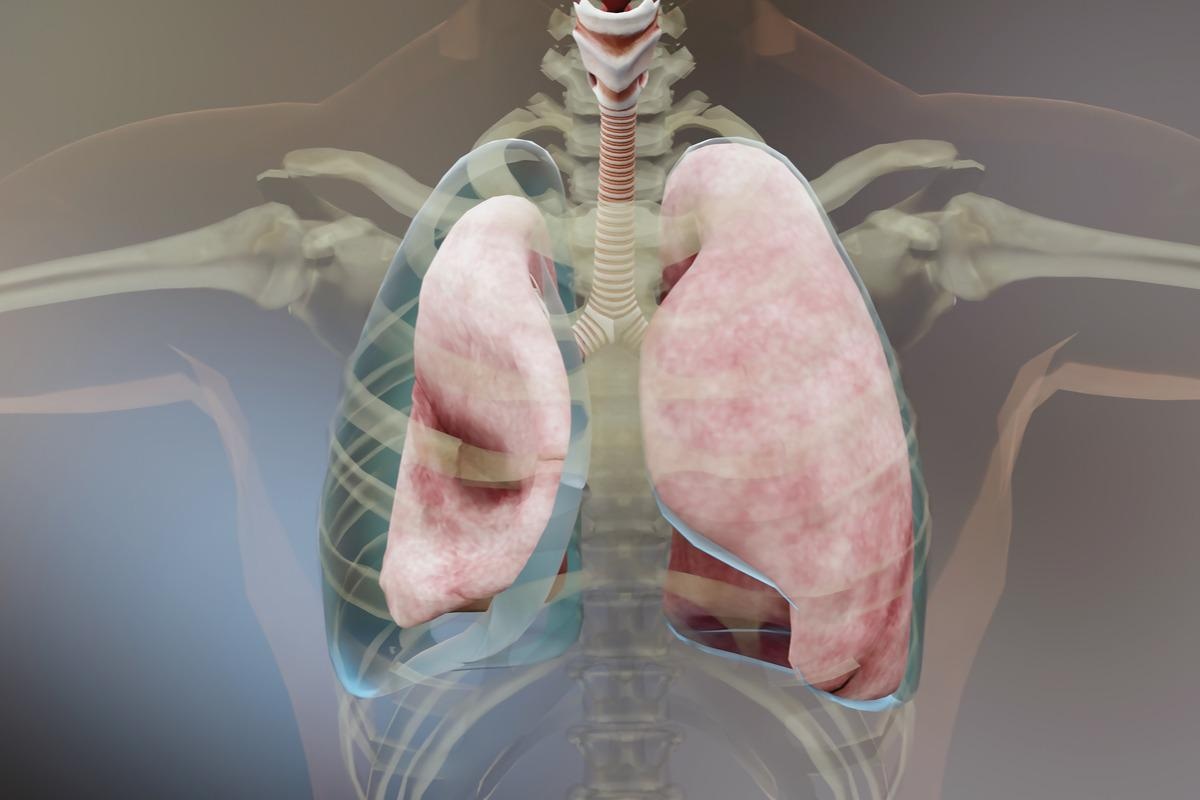

Empyema is a medical term used for pus pockets that have accumulated inside a body cavity, for example, pleural space. This condition occurs when a bacterial infection remains untreated or if it does not respond completely to treatment.

Empyema is a severe condition that necessitates medical attention. It can cause chest pains, coughing up mucus, fever, and shortness of breath.

A pleura is a smooth layer that covers the interiors of the chest cavity and lungs. A thin space known as pleural space is filled with pleural fluid that separates these layers, which are almost in contact. This fluid sometimes accumulates and becomes infectious, and the collection of pus begins, which thickens and leads to the sticking of the pleural layers, forming pus pockets. As the accumulation of the fluid increases, the pus pockets increase, and the thick fluid begins coating the outer layer of the lungs blocking them from expanding and worsening the empyema.